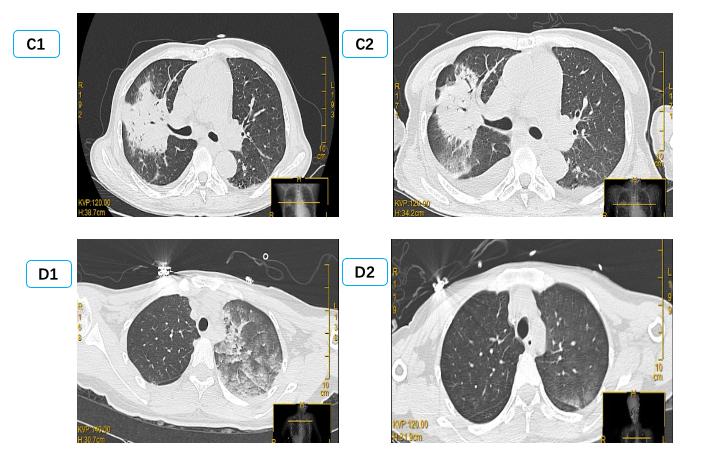

1.3 病例分组根据影像学表现分为双侧PE组和单侧PE组。单侧PE包括右侧和左侧PE(图 1图 2)。

| (C1、C2为同一患者,右侧PE,男,56岁,冠状动脉搭桥术后,C1为咳嗽咳痰1周入院时,C2为抗感染治疗14 d后。D1、D2为同一患者,左侧PE,女,32岁,眼眶下局麻后心脏骤停,D1为心脏骤停后3 h,D2为心脏骤停后24 h。) 图 2 单侧肺水肿CT表现 Fig 2 Manifestations of unilateral PE on CT |

2 结果通过病历系统回顾性分析2018年1月至2021年1月,共纳入314例患者,其中男性179例,女性135例,年龄18~97岁[(58.8±16.9)岁]。单侧PE患者共14例,发病率4.5%,男性10例,女性4例; 其中以右侧为主单侧PE 11例(78.5%),左侧PE患者3例(21.5%)。1例单侧PE呈右肺上叶局限性分布,(见图患者C),1例单侧PE以左下肺为主(见图患者A),其余单侧PE分布无明显肺段特点。

在本次试验中单侧PE发生率为4.5%,高于国外心内科单侧PE 2.1%发病率[2]。同时本次14例单侧PE中,主要(11例,78.5%)为右侧PE,与国外研究类似(16例,89%)[2]。本研究中,两组间左心室射血分数、左心房前后径、左心室舒张末内径等心脏超声参数均差异无统计学意义,与既往研究类似。同时该研究发现单侧PE患者重度二尖瓣反流比例高达100%[2]; 提示二尖瓣反流是导致单侧PE的主要原因。本研究中重度二尖瓣反流在单侧PE组发生率显著高于双侧PE组,35.7% vs 14.0%,但显著低于前述研究,可能与患者纳入标准有关,有5例(35.7%)因心室颤动等原因导致心脏骤停。其中如图 2中D患者,女,32岁,眼眶下局麻后心脏骤停。心脏骤停后3 hCT提示左肺弥漫渗出,但复苏8 h后查心脏超声无明显二尖瓣反流,考虑与心脏骤停冠脉缺血导致暂时性二尖瓣反流有关[25-26],因此24 h后复查CT左肺单侧PE完全消失。

除考虑二尖瓣偏心反流导致单侧或单支肺静脉压力升高,回流受阻,还可能与双侧肺静脉回流角度、大小有关。研究显示左心房入口处,右侧肺静脉相比左侧肺静脉其内径、横截面积均更大[27],同时右肺静脉与二尖瓣反流的角度更小,因此在二尖瓣导致的单侧PE以右侧为主[2],尤其是右上叶为主[9, 11],部分患者PE表现非常局限,常常误诊为肺部感染[9, 28],如图 2中C患者。但本研究中心脏骤停患者,心肺复苏按压时双侧肺静脉回流阻力是否有影响目前尚不明确。